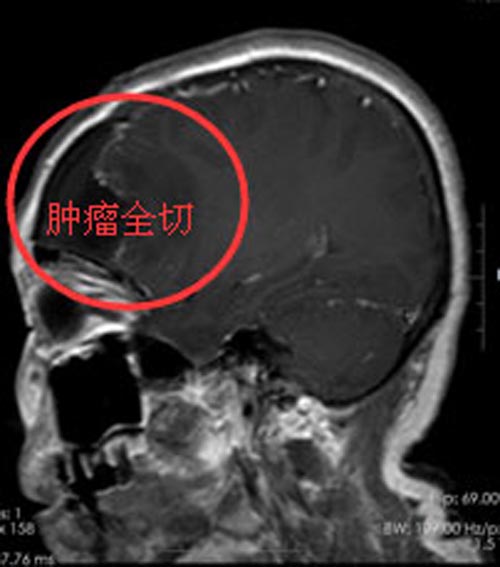

家人都觉得手臂的事小,脑肿瘤的事不小,赶紧陪着她来到了广东三九脑科医院入住综合神经外科。由于肿瘤占位效应明显,医生建议手术治疗,排除手术禁忌症后,在全麻下为黄阿姨行“经右额行右侧额部肿瘤切除术”,术中可见肿瘤血供丰富,显微镜下整块全切肿瘤,术程顺利。术后第三天,黄阿姨言语对答切题,视力视野未见异常,除摔伤的左上肢肌力III级外,余肢体肌力肌张力正常。术后病理:脑膜皮细胞型脑膜瘤。